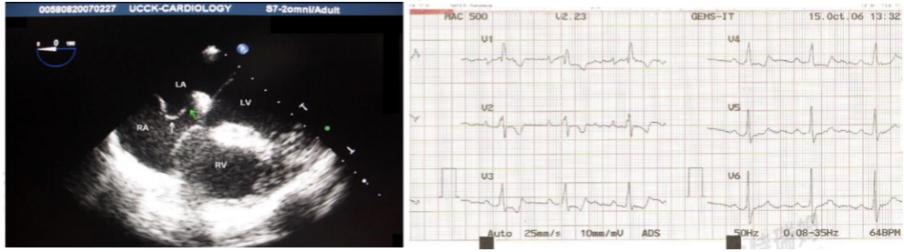

同时,不完全右束支阻滞提示房间隔缺损面积较大。如图15示:42岁中年女性,心电图示:右束支阻滞;心脏超声提示:卵圆孔未闭:4.5mm。

图15:卵圆孔未闭